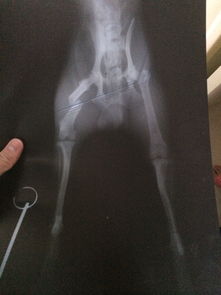

看了你追加描述和圖片,基本確定是骨折!不打算去醫(yī)院的話就按照我上面說(shuō)的做,狠狠心找到骨折的地方,試著做一下整復(fù),外邊用硬紙殼固定!可以去買(mǎi)一些人藥!狗狗會(huì)很快好起來(lái)的

我家狗狗一歲之前前腿骨折, 拍片和你這個(gè)情況看起來(lái)差不多. 沒(méi)有做麻醉和內(nèi)固定手術(shù). 做的是外固定, 不過(guò)做好外固定以后就要注意補(bǔ)鈣, 一個(gè)月左右, 就好了. 平時(shí)要看好它. 不能讓它亂動(dòng), 特別是睡覺(jué)之前要確定它能正常躺下, 躺下和站起來(lái)的過(guò)程是比較痛的. 小狗的恢復(fù)能力比人強(qiáng)很多, 他們的代謝速度是我們的好幾倍. 所以也不需要太擔(dān)心了. 但是如果一定要做手術(shù)的話, 鋼針一定要取出來(lái)的. 至于麻藥的風(fēng)險(xiǎn), 不能說(shuō)沒(méi)有. 我家的做絕育手術(shù)也用了全身麻醉, 有各別狗狗會(huì)有過(guò)敏性休克. 但是幾率很低.至于這個(gè)南瓜子,我沒(méi)有喂過(guò). 不過(guò)如果是我要喂狗狗吃的話, 應(yīng)該會(huì)磨碎或者弄小顆拌狗糧, 它就會(huì)吃. 我家的是吃貨, 不挑食的. 假如挑食的話, 可以稍微烤一下嘛, 香一點(diǎn)自然會(huì)吃啦! 其實(shí)狗狗真的好的很快的. 最主要的是看好它不要讓它亂動(dòng)重復(fù)受傷, 如果接好了以后固定住了又錯(cuò)位, 就很麻煩了. 還有接不好或者又亂動(dòng)錯(cuò)位了還給長(zhǎng)好了, 就很可能變成長(zhǎng)短腿或者Z型腿. 如果對(duì)你有幫助記得采納哦。